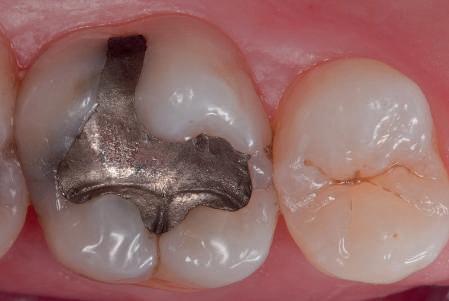

Materialele compozite reprezintă un alt exemplu de proces revoluţionar al paradigmelor. Restaurările din silicat şi amalgam sunt aproape dispărute, în ciuda anumitor calităţi ce le caracterizează. Evoluţia spre compozite performante a fost facilitată de cercetările aprofundate ale proprietăţilor lor fizice, inovaţiile din acest domeniu avansând în paralel cu doleanţele estetice ale societăţii moderne.